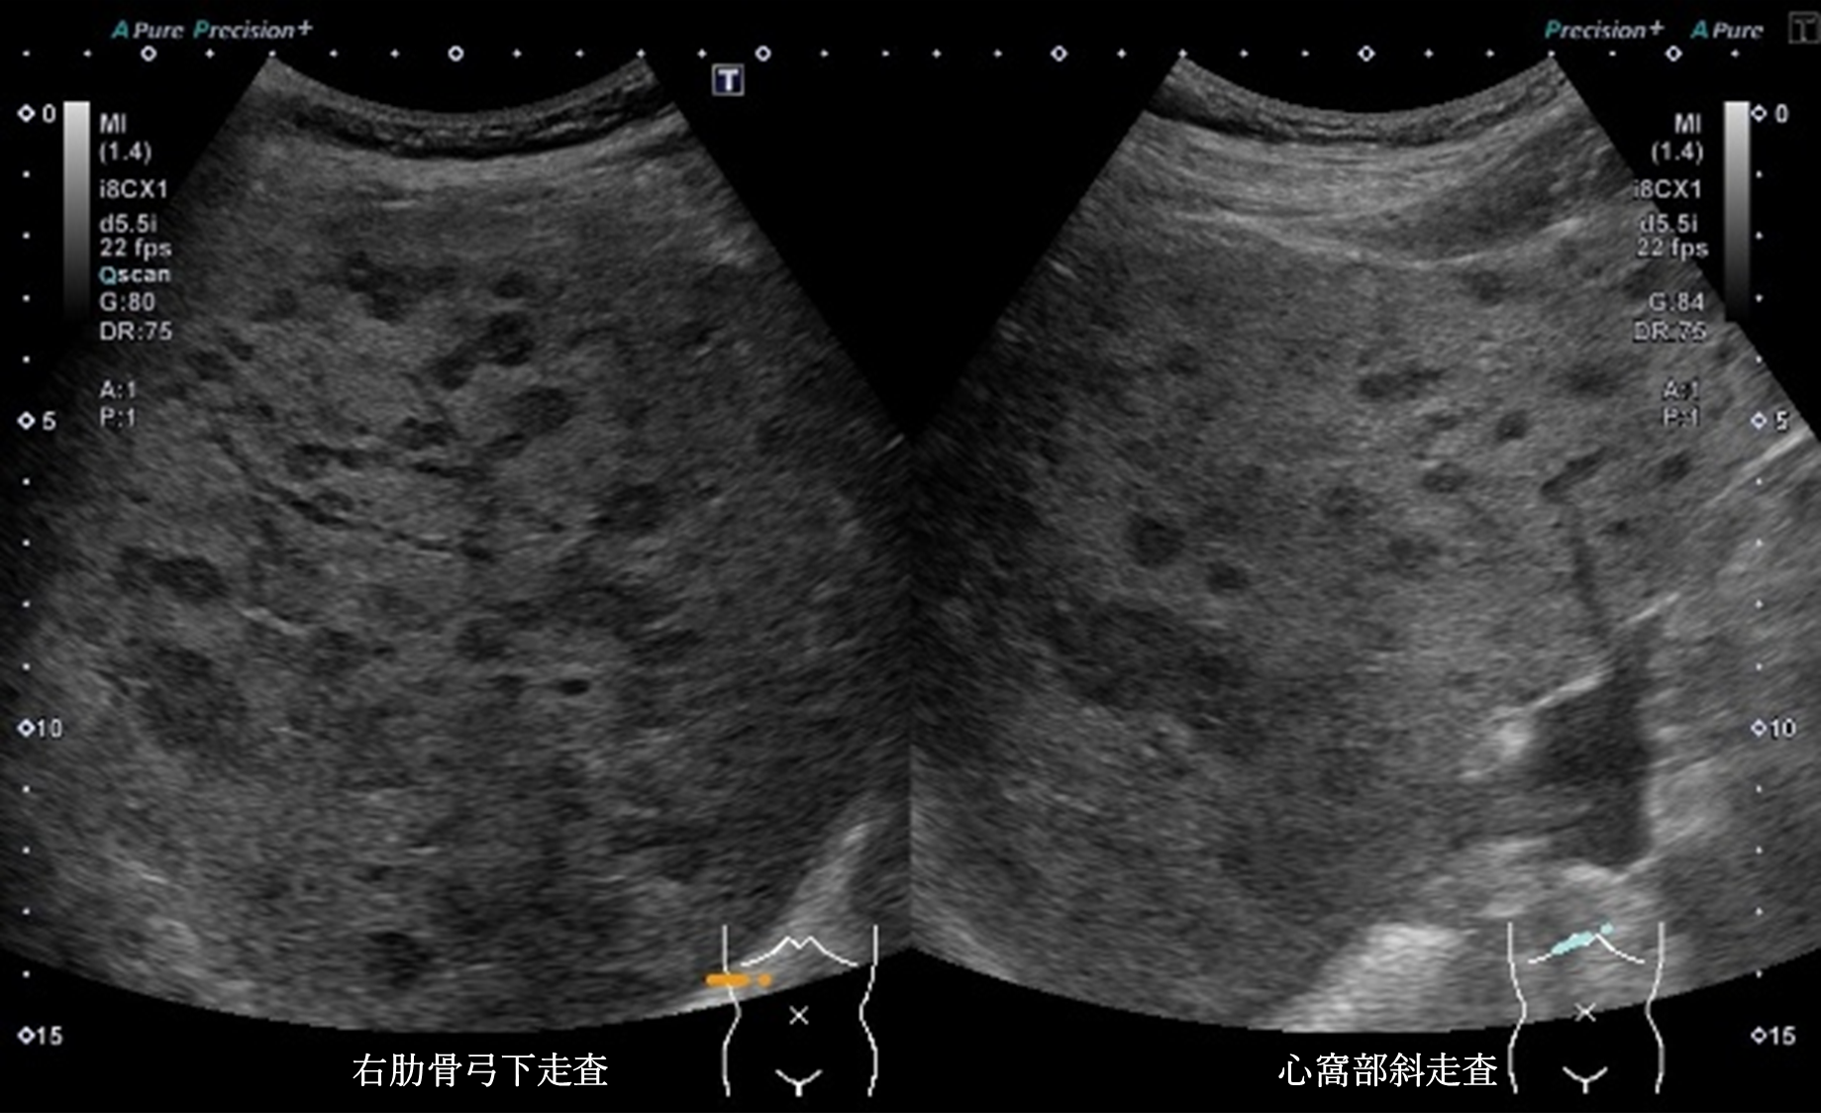

静止画4枚、動画1枚を示す。

腹部超音波画像 画像1(No16-17_1)画像2(No16-17_2)画像3(No16-17_3)画像4(No16-17_4)

超音波所見より正しいのはどれか

① 肝全体に内部無エコーな腫瘤性病変を多数認める

② 肝全体に腫瘤性病変が多数みられ、辺縁低エコー帯を認める

③ 肝実質は粗雑不均質に観察され、明らかな腫瘤性病変は指摘できない

④ 肝全体に腫瘤性病変が多数みられ、腫瘤内部はモザイクパターンを呈する

⑤ 肝全体に腫瘤性病変が多数みられ、腫瘤辺縁にリング状高エコー像を認める

静止画および動画から超音波所見と考えられる疾患の組み合わせで正しいものはどれか

④ bull’s eye pattern ― 転移性肝腫瘍